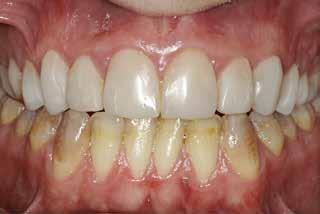

Fig. 1. 40-årig sund og rask mand møder bekymret for sine slidte tænder. Klinisk ses frakturer og substanstab langs incisalkanterne på overkæbetænderne.

Fig. 1. A 40-year-old healthy man is concerned for his worn teeth. Clinically, fractures and loss of tooth substance are observed at the incisal edge of the upper front teeth.

Postoperativ status

Fig. 4. Færdigrestaurerede tænder med komposit.

Fig. 4. Final restored teeth with composite.